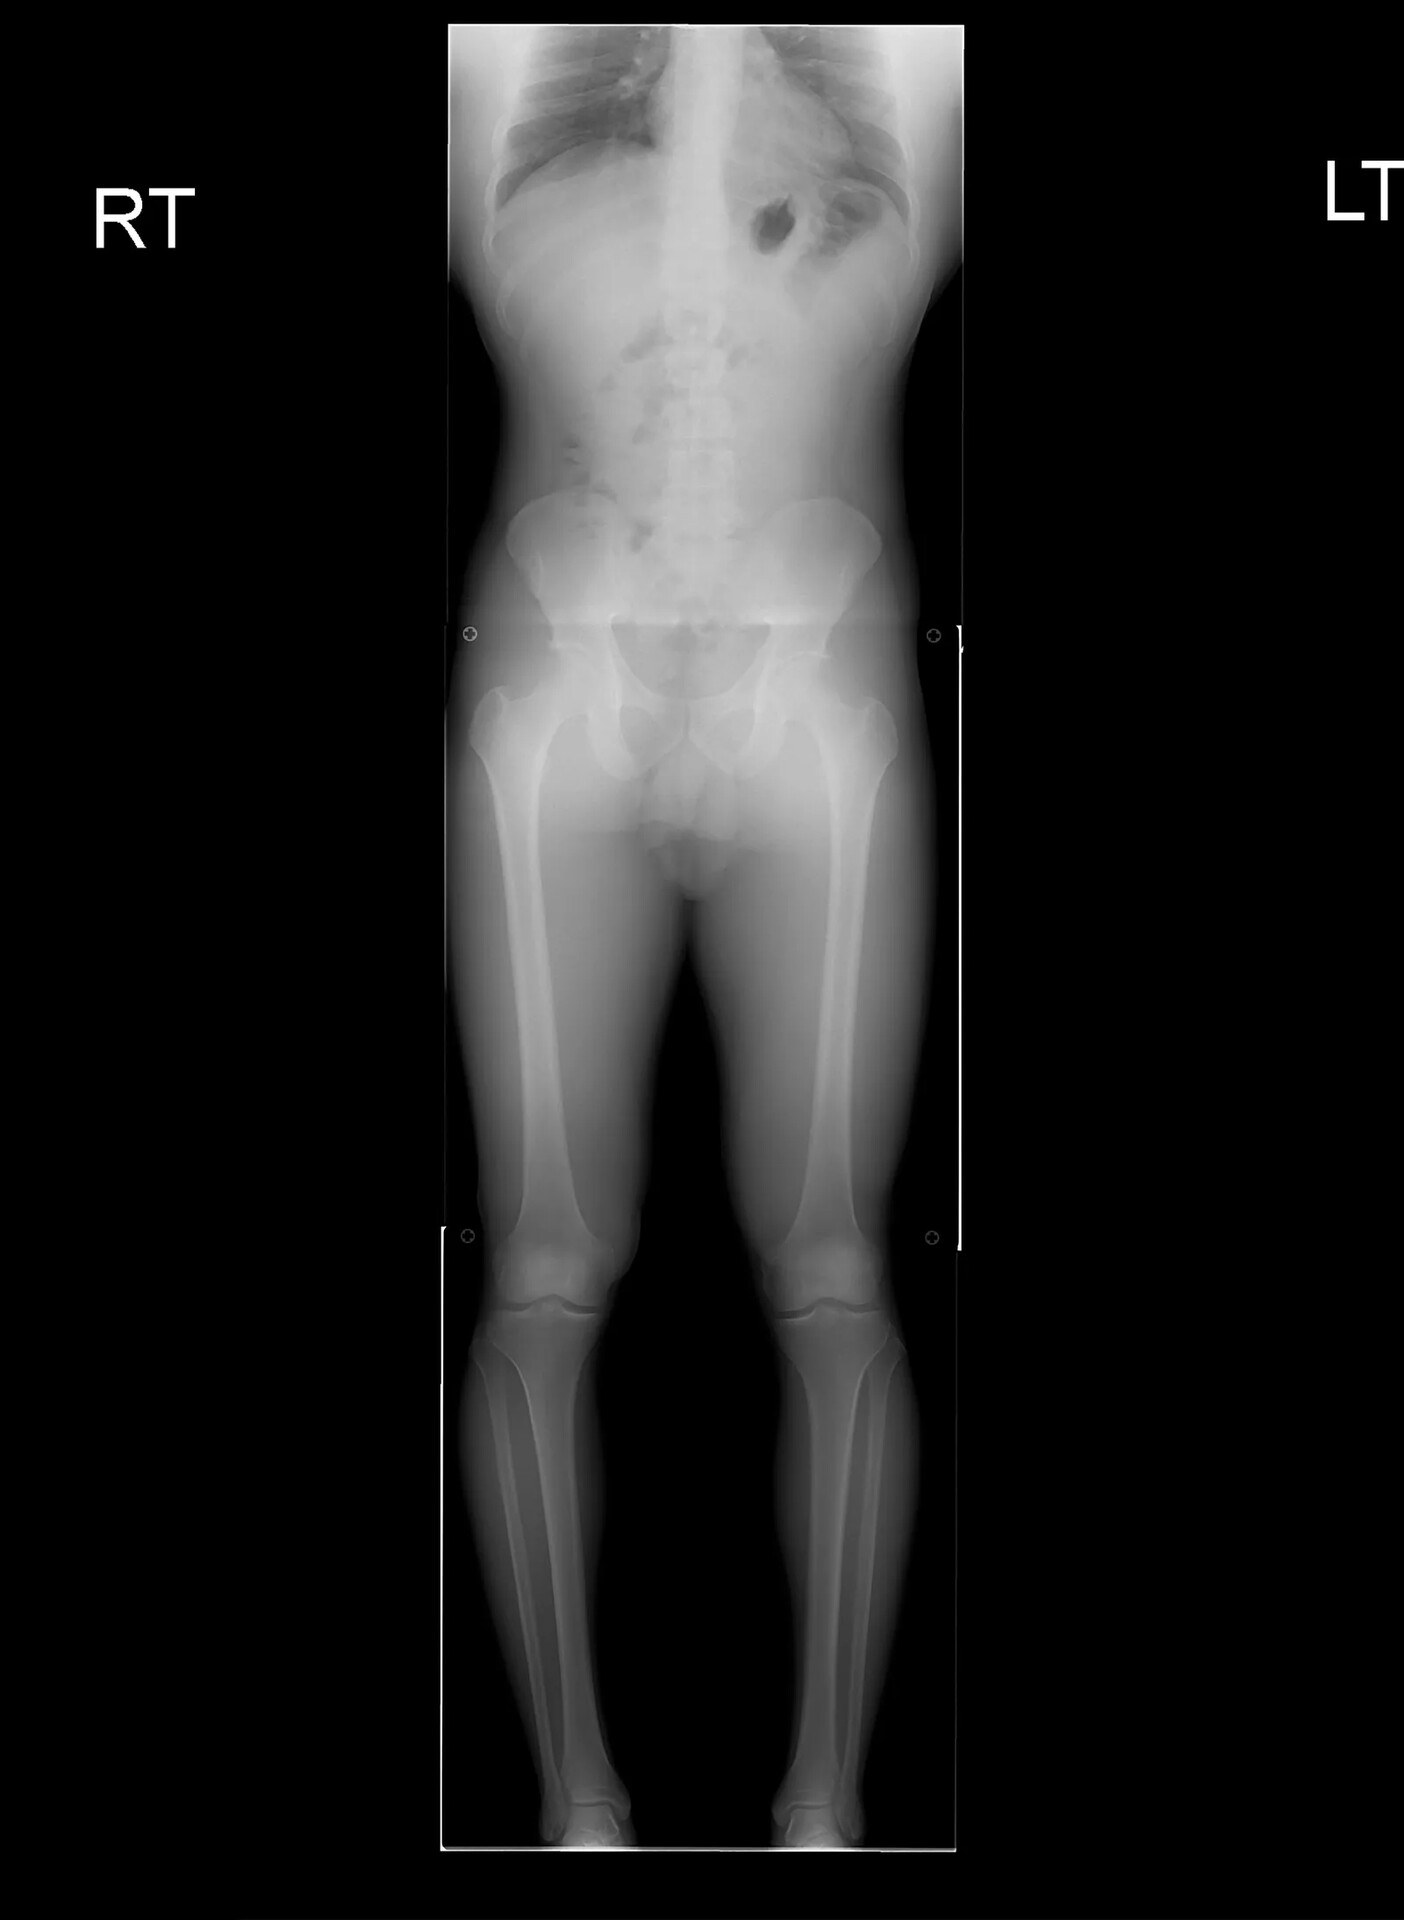

Ένα από τα πιο δύσκολα ζητήματα που αντιμετωπίζουν οι άντρες σε σχέση με την αυτοεικόνα τους φαίνεται να είναι το ύψος. Το ύψος ενός άντρα είναι μεγάλο προτέρημα ή μειονέκτημα. Στα social media, το να κοροϊδεύεις έναν άντρα για το ύψος του μοιάζει να είναι μια κοινωνικά αποδεκτή μορφή body shaming. Η ανασφάλεια αυτή απέκτησε πρόσφατα χειρουργική λύση: πλέον, ένας άντρας μπορεί να ξοδέψει πενταψήφιο ή εξαψήφιο ποσό για να σπάσει τα κόκαλα των ποδιών του και να τα μακρύνει, με μια χειρουργική τεχνική που βασίζεται στην αναγέννηση των οστών. Η επέμβαση είναι ακριβή, επώδυνη, αυξημένης επικινδυνότητας και όποιος την κάνει θα περάσει μήνες στο κρεβάτι και θα πρέπει να μάθει να περπατάει απ’ την αρχή.

Πολλά είναι τα ερωτήματα που είναι δύσκολο ν’ απαντηθούν σχετικά με την επέμβαση: το αν οι άνθρωποι αυτοί μπορούν να χρησιμοποιούν τα πόδια τους όπως πριν, αν μπορούν να πηδάνε στην άθληση, αν θα έχουν μακροπρόθεσμες αρνητικές συνέπειες που θα εμφανιστούν μετά από δύο ή τρεις δεκαετίες, καθώς και αν θα χρειαστούν επιπρόσθετες επεμβάσεις για να επανέλθει το σώμα στην προηγούμενη κατάσταση.

Σε διάφορα forum στο διαδίκτυο, δεν είναι λίγοι οι άντρες που μοιράζονται την εμπειρία τους. Ως επί το πλείστον, οι γνώμες που διάβασα είναι θετικές. Πιστεύουν ότι η επέμβαση άξιζε. Πολλές ιστορίες προσθέτουν πληροφορίες που μας αφήνουν να φανταστούμε την κοινωνική πίεση που βίωναν: άλλοι μιλούν για το bullying που υπέστησαν ως παιδιά επειδή ήταν κοντοί, άλλοι γράφουν ότι η επέμβαση τούς έδωσε τη δυνατότητα να αποκτήσουν επιτέλους κύρος στην εργασία τους και άλλοι γράφουν ότι απέκτησαν άλλη αυτοπεποίθηση στη συναναστροφή τους με τις γυναίκες. Στα ίδια forum, πολλοί είναι οι άντρες που γράφουν πως η απόφαση αυτή τούς φαίνεται μονόδρομος και αν είχαν τα χρήματα θα την έκαναν. Ένας άνδρας που ψήλωσε 7,5 εκατοστά καταλήγει στο εξής συμπέρασμα, 8 μήνες μετά την επέμβαση: «Έχω ακόμη τις ουλές σαν αναμνηστικά και θυμάμαι την προηγούμενη ζωή μου όταν λέω κάποιο ψέμα για το πώς τις απέκτησα. Περπατάω κανονικά τώρα, αλλά δεν μπορώ να τρέξω καλά. Δεν κάνω πολλές ασκήσεις ποδιών, κυρίως περπατάω. Δεν πιστεύω ότι θα επανέλθω ποτέ στο 100%. Για την ακρίβεια, είμαι σίγουρος ότι δεν θα επανέλθω. Αυτή είναι μια θυσία που έκανα με αντάλλαγμα μια καλύτερη ζωή».